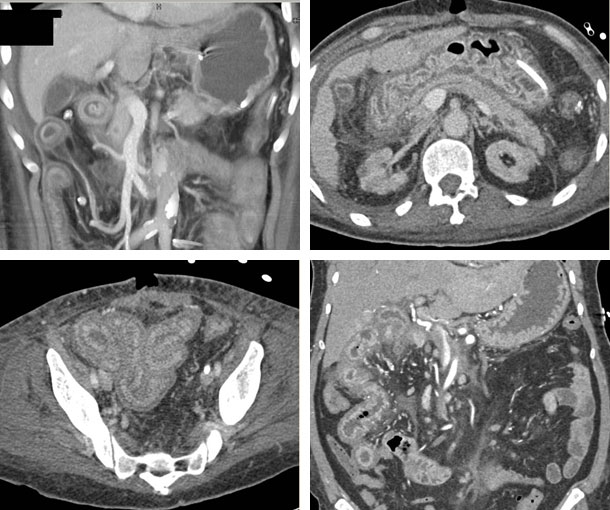

Chemotherapy-Induced Enteritis CT Findings

- CT findings include "halo" and associated mesenteric involvement